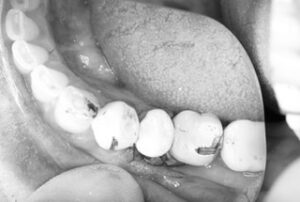

首都圏に不要不急の外出禁止要請が発令されてる中ですが、浅草橋の須田歯科クリニック分院では『食事をちゃんと取りたい』と希望される患者さんの右下5番の抜歯即時埋入のオペが朝からありました。

切開、抜歯から埋入、縫合までの全てを20分で終了。

その後は密着具合を示す値も良く、即日に仮歯まで装着してお帰り頂きました。